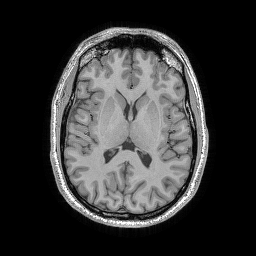

Brain TSE. We used a turbo spin-echo sequence on a 3T scanner to acquire a T2-weighted human brain image using a 32-channel receiver array, as depicted in Fig. 1(b).